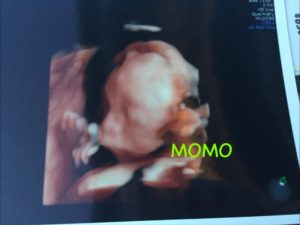

そしてまさかの男の子!(笑)

その後無事に3900gの大きくて元気な男の子を生みました。